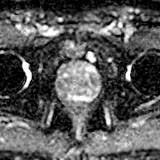

冠状位

T2加权像

前列腺增大,大小为52 x 56 x 57 mm(体积87 ml)。

在前列腺中部/尖部,右侧外周带/周围膜交界处可见一大小为7 x 5 mm的毛刺状、边界不清的T2低信号病灶,伴有扩散受限和早期动脉期强化,提示为PI-RADS 4级病灶。